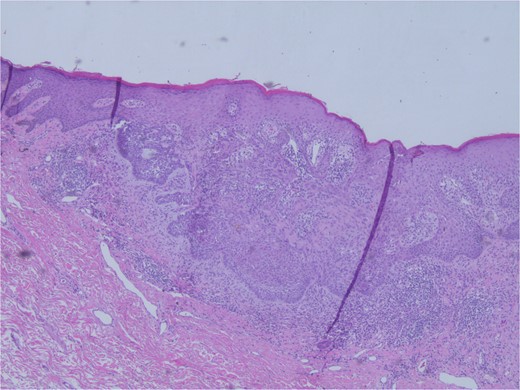

At the time of the surgery, the lesion was excised with 5 mm margins, given the acceptable margins of 4 mm for nonmelanoma skin cancer [4]. Macroscopic examination of the lesion revealed a well-defined, hyperpigmented, macular lesion with pathology positive for infiltrating BSC with negative margins confirmed on histology. Histology was notable for predominantly basal cell morphology with areas of squamous differentiation. The presence of the basal cell carcinoma component is demonstrated (Fig. 1). The BSC with abnormal squamous keratinization is also demonstrated (Figs 2–4). These studies were conducted on routine hematoxylin and eosin stains confirming the diagnosis of BSC. The patient was seen in the office, and at 2 months postoperative, there were no clinical concerns.

Microphotograph revealing BSC with abnormal squamous keratinization on histology.